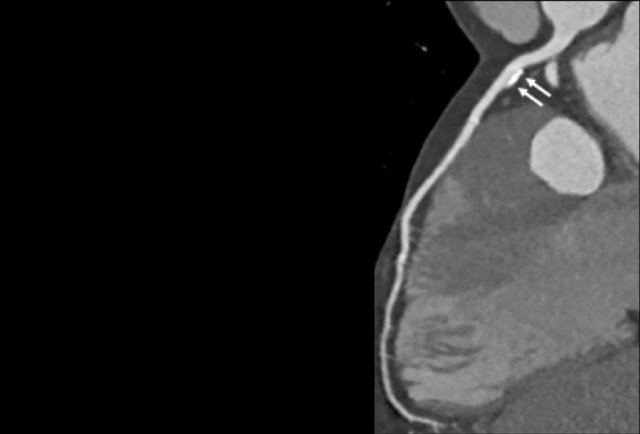

Same patient. First, study the CTA image.

How would you describe the findings?

The coronal image shows a central low-attenuation area around the lumen

of the LAD.

This low-attenuation area is surrounded by a higher attenuation

area.

This finding is the earlier discussed napkin-ring sign, which is a high-risk

plaque feature.

This patient classifies as CAD-RADS 4A/P1/HRP.

Same patient.

Double-oblique (A) and volume-rendered (B) images of the LAD showing the

location and the length of the plaque.

Also, the stenosis in the D2 branch of the LAD can be appreciated on the volume

rendered reconstruction.